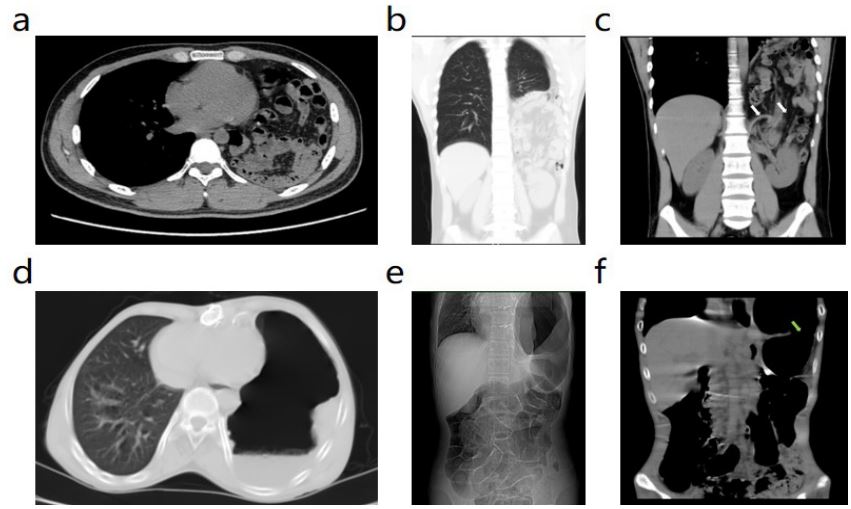

Postoperative follow-up: The patients were followed up for 6-12 months, with an average of 8.5 months. During the follow-up period, no recurrence of diaphragmatic hernia was found by chest and abdominal CT (Figure 3), and no chronic postoperative pain, intestinal adhesion, or pulmonary atelectasis occurred.

Figure 3: Postoperative follow-up CT findings in patients with diaphragmatic hernia. (a-c) Follow-up CT of Case 1 1 month after surgery showed good lung recruitment and no recurrence of diaphragmatic hernia. (d-f) The follow-up CT of Case 2 at 6 months after operation showed that the left lung was fully re-expanded, and there was no diaphragmatic defect or recurrence